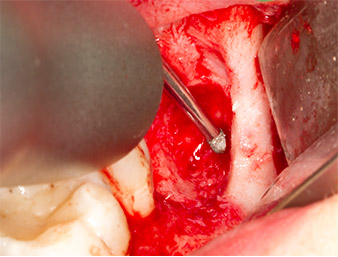

A continuación, se utilizó un inserto para la retirada de los sedimentos periodontales (Piezomed P1) y se amplió mínimamente el surco periodontal del resto radicular (figura 8).

El mismo inserto activado se introdujo en el canal radicular y aflojó el fragmento gracias a sus vibraciones microoscilantes (figuras 9 y 10).